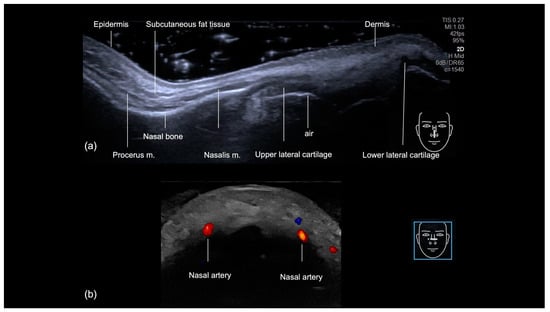

3.1.1. Sonographic Anatomy of the Nose

3.1.2. Ultrasound-Guided Filling Techniques of the Nose